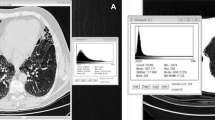

To evaluate the feasibility of automated quantitative analysis with a three-dimensional (3D) computer-aided system (i.e., Gaussian histogram normalized correlation, GHNC) of computed tomography (CT) images from different scanners.

Each institution’s review board approved the research protocol. Informed patient consent was not required. The participants in this multicenter prospective study were 80 patients (65 men, 15 women) with idiopathic pulmonary fibrosis. Their mean age was 70.6 years. Computed tomography (CT) images were obtained by four different scanners set at different exposures. We measured the extent of fibrosis using GHNC, and used Pearson’s correlation analysis, Bland–Altman plots, and kappa analysis to directly compare the GHNC results with manual scoring by radiologists. Multiple linear regression analysis was performed to determine the association between the CT data and forced vital capacity (FVC).

For each scanner, the extent of fibrosis as determined by GHNC was significantly correlated with the radiologists’ score. In multivariate analysis, the extent of fibrosis as determined by GHNC was significantly correlated with FVC (p < 0.001). There was no significant difference between the results obtained using different CT scanners.

Gaussian histogram normalized correlation was feasible, irrespective of the type of CT scanner used.